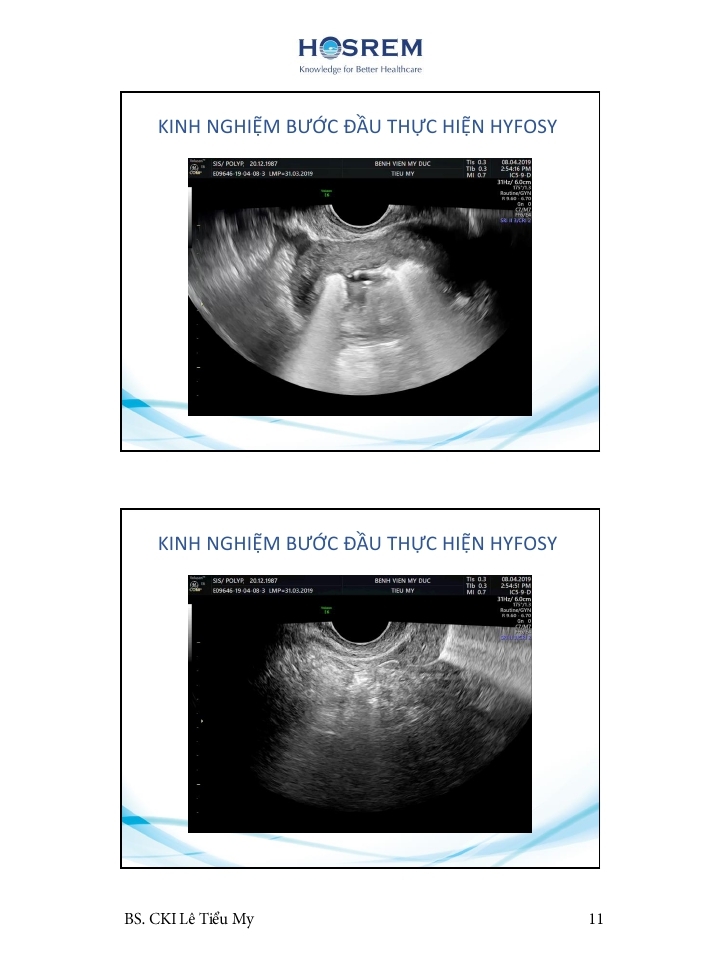

Các phương pháp đánh giá ống dẫn trứng